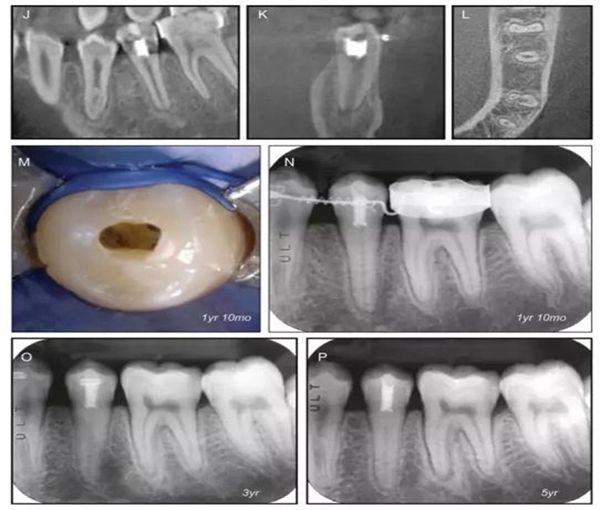

原則上年輕恒牙的牙髓治療應(yīng)盡可能以保存活髓的方式以便不影響牙根繼續(xù)發(fā)育。本文3個(gè)病例均描述了根尖尚未發(fā)育完成的下頜前磨牙被確診為牙髓壞死伴有大面積根尖病損,治療過程中在根管內(nèi)發(fā)現(xiàn)了部分活髓,而采用活髓切斷后都取得了很好的療效。